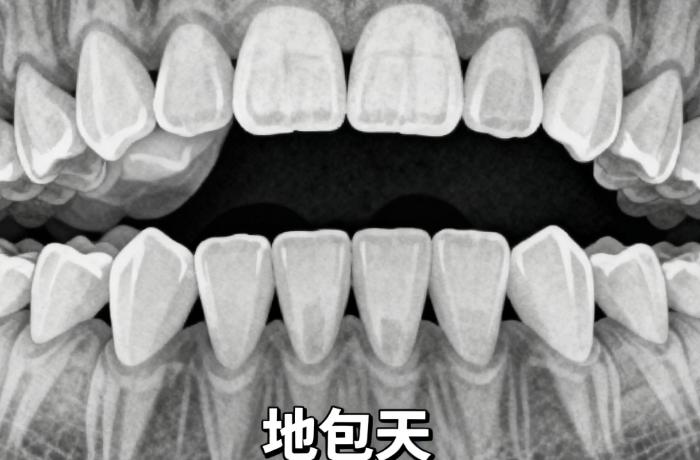

想在永州給牙齒做個(gè)“立正”,卻又擔(dān)心水深坑多、預(yù)算超標(biāo)?今天就給大家?guī)硪环輰?shí)實(shí)在在的硬核攻略:永州德皓口腔矯正牙齒價(jià)格標(biāo)。這對于咱們永州本地想看牙的學(xué)生黨和上班族來說,簡直是福音。

很多姐妹問:“為什么一定要選德皓?”其實(shí)較打動(dòng)人的就是這份價(jià)格表的坦誠。為了讓大家心里有底,我特意羅列了院內(nèi)涵蓋各類主流矯正及相關(guān)項(xiàng)目的參考價(jià)格,共計(jì)不少于8個(gè)核心項(xiàng):